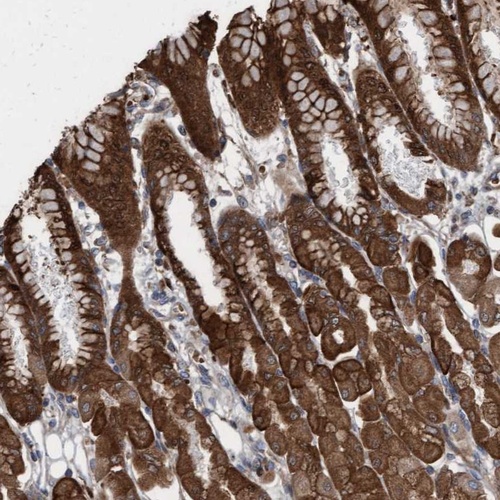

Immunohistochemical staining of human stomach shows strong cytoplasmic and nuclear positivity in glandular cells.